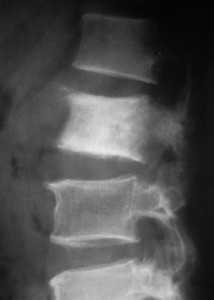

Рентгенологически метастазы могут быть остеолитическими (молочная железа, лёгкие, почки, щитовидная железа), склеротическими (предстательная железа, иногда молочная железа, толстая кишка, меланома, мочевой пузырь, мягкие ткани) или смешанными. Рентгенографическими признаками метастазов являются грубый компрессионный перелом позвонка, полная или частичная его деструкция и (или) участки измененной плотности. Типично вовлечение дуг и замыкательных пластин. Очевидный лизис наступает только после потери 50-70% костных балок, а кортикальная деструкция появляется только на завершающем этапе. Дифференциальная диагностика с доброкачественными компрессионными переломами не всегда легко решается. Главным недостатком рентгенографии является невозможность оценки распространения вторичной опухоли на мягкие ткани, в первую очередь эпидуральное пространство. Приходится прибегать к миелографии, которая связана с определенным риском осложнений.

Рентгенограмма в боковой проекции. Метастаз рака предстательной железы.